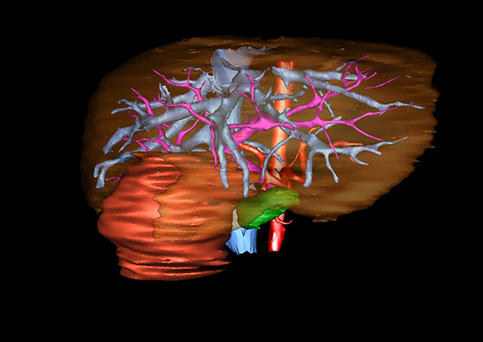

近年来由于数字医学的发展,基于可视化三维重建技术的计算机辅助手术系统极大推进了小儿肝脏肿瘤的精准手术的进步。可以立体透视肝脏解剖、精确掌握肝段的边界、精确测算肝段乃至任意血管所支配的功能体积、准确定位病灶及其与邻近血管的解剖关系,最终对不同手术方案进行比较、筛选和优化。因此,计算机辅助手术规划系统是实现精准肝切除的有力辅助工具,是未来数字外科、精准外科等21世纪外科新理念的重要技术支撑。

计算机辅助手术规划系统具有良好的操作可行性、计算准确性和三维显示效果,可半透明、交互式显示真实的肝内立体解剖关系和空间管道变异,准确计算肝内管道的直径、走行角度,两点间的垂直距离,和任意血管的支配或引流范围等传统二维影像无法获取的信息,有助于实施个体化手术,提高了手术的确定性、预见性和可控性。计算机辅助手术规划系统可直观显示预留肝脏的结构和功能,并可通过虚拟切割功能辅助术者对手术方案进行蹄选和优化,系统评估手术风险和制定对策,改变了部分二维规划的术式和切除范围,使部分二维规划认为不能切除的患者成功手术,提高了手术的根治性、安全性和病变的可切除性,更加符合精准肝脏外科的术前规划要求。详见第11章。

随着计算机技术及影像检查技术的不断发展,以精确的术前影像学和功能评估、精细的手术操作为核心的精准肝切除技术日益受到重视。基于数字医学的计算机辅助手术技术(computer-assisted surgery,CAS)则是实现肝脏精准手术操作的基础。计算机辅助手术系统(CAS)可将术前二维(two dimensional,2D)的CT/MRI影像数据进行三维(three dimensional,3D)重建,建立个体化的肝脏三维解剖模型,清晰显示肝脏内脉管系统的走行及解剖关系,还原病灶与其周围脉管结构的立体解剖构象,准确地对病变进行定位、定性和评估,制定合理、定量的手术方案,实施个体化的肝脏血管取舍分配方案及实施精准肝脏手术。一般认为CAS包括:创建虚拟的患者的图像;患者图像的分析与深度处理;诊断、手术前规划、手术步骤的模拟;术中实时导航。应用本技术后,由于可以更清晰地看出肿瘤的界限,特别是根据肝血管的显影,判断出肿瘤与门静脉及肝静脉的关系以在手术前较准确地估计出手术成功切除的可行性。以往部分根据普通强化CT判断无法手术的病例而被评估为可以成功切除并手术成功。